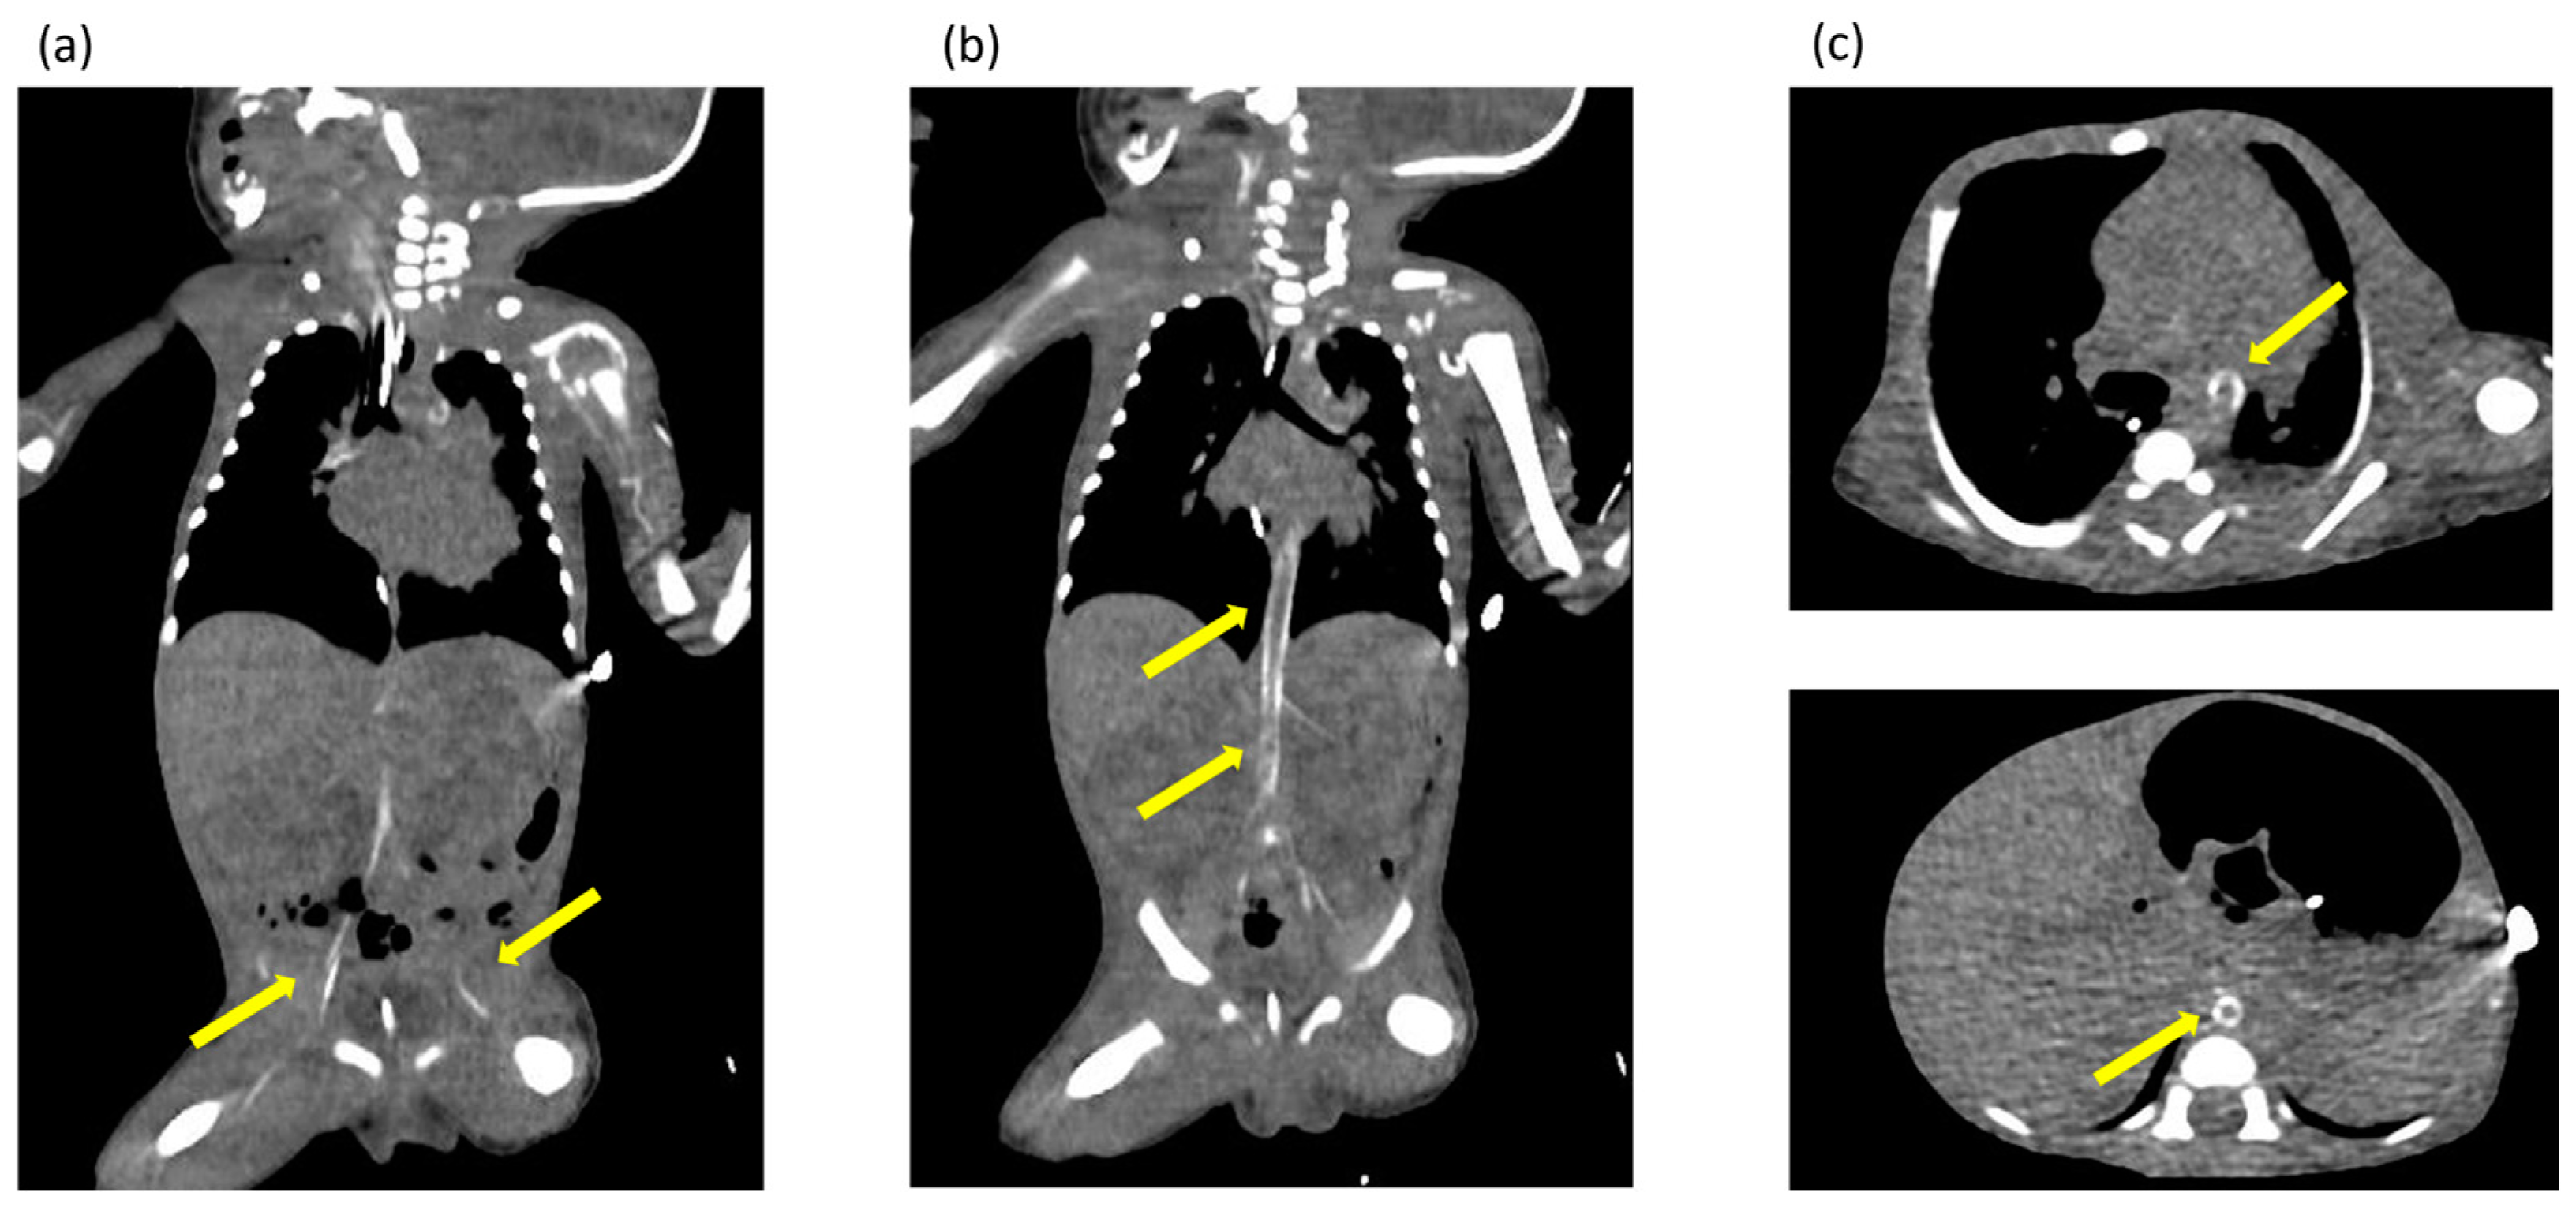

Ultrasonography of the chest revealed enhanced high-intensity lesions of the arterial walls. The high-intensity lesion persisted and gradually intensified. We suspected calcification of the blood vessels and performed CT at 17 days of age, which revealed calcification of the arterial walls in her whole body (Figure 2). No extravascular calcification was noted, and medullary nephrocalcinosis was not seen. We diagnosed the patient with GACI due to severe arterial calcification.

Figure 2.

(a–c) Computed tomography images obtained at 17 days of age showing extensive calcification of the arterial walls throughout the body. The yellow arrows indicate areas of calcification identified in the arterial wall throughout the body.